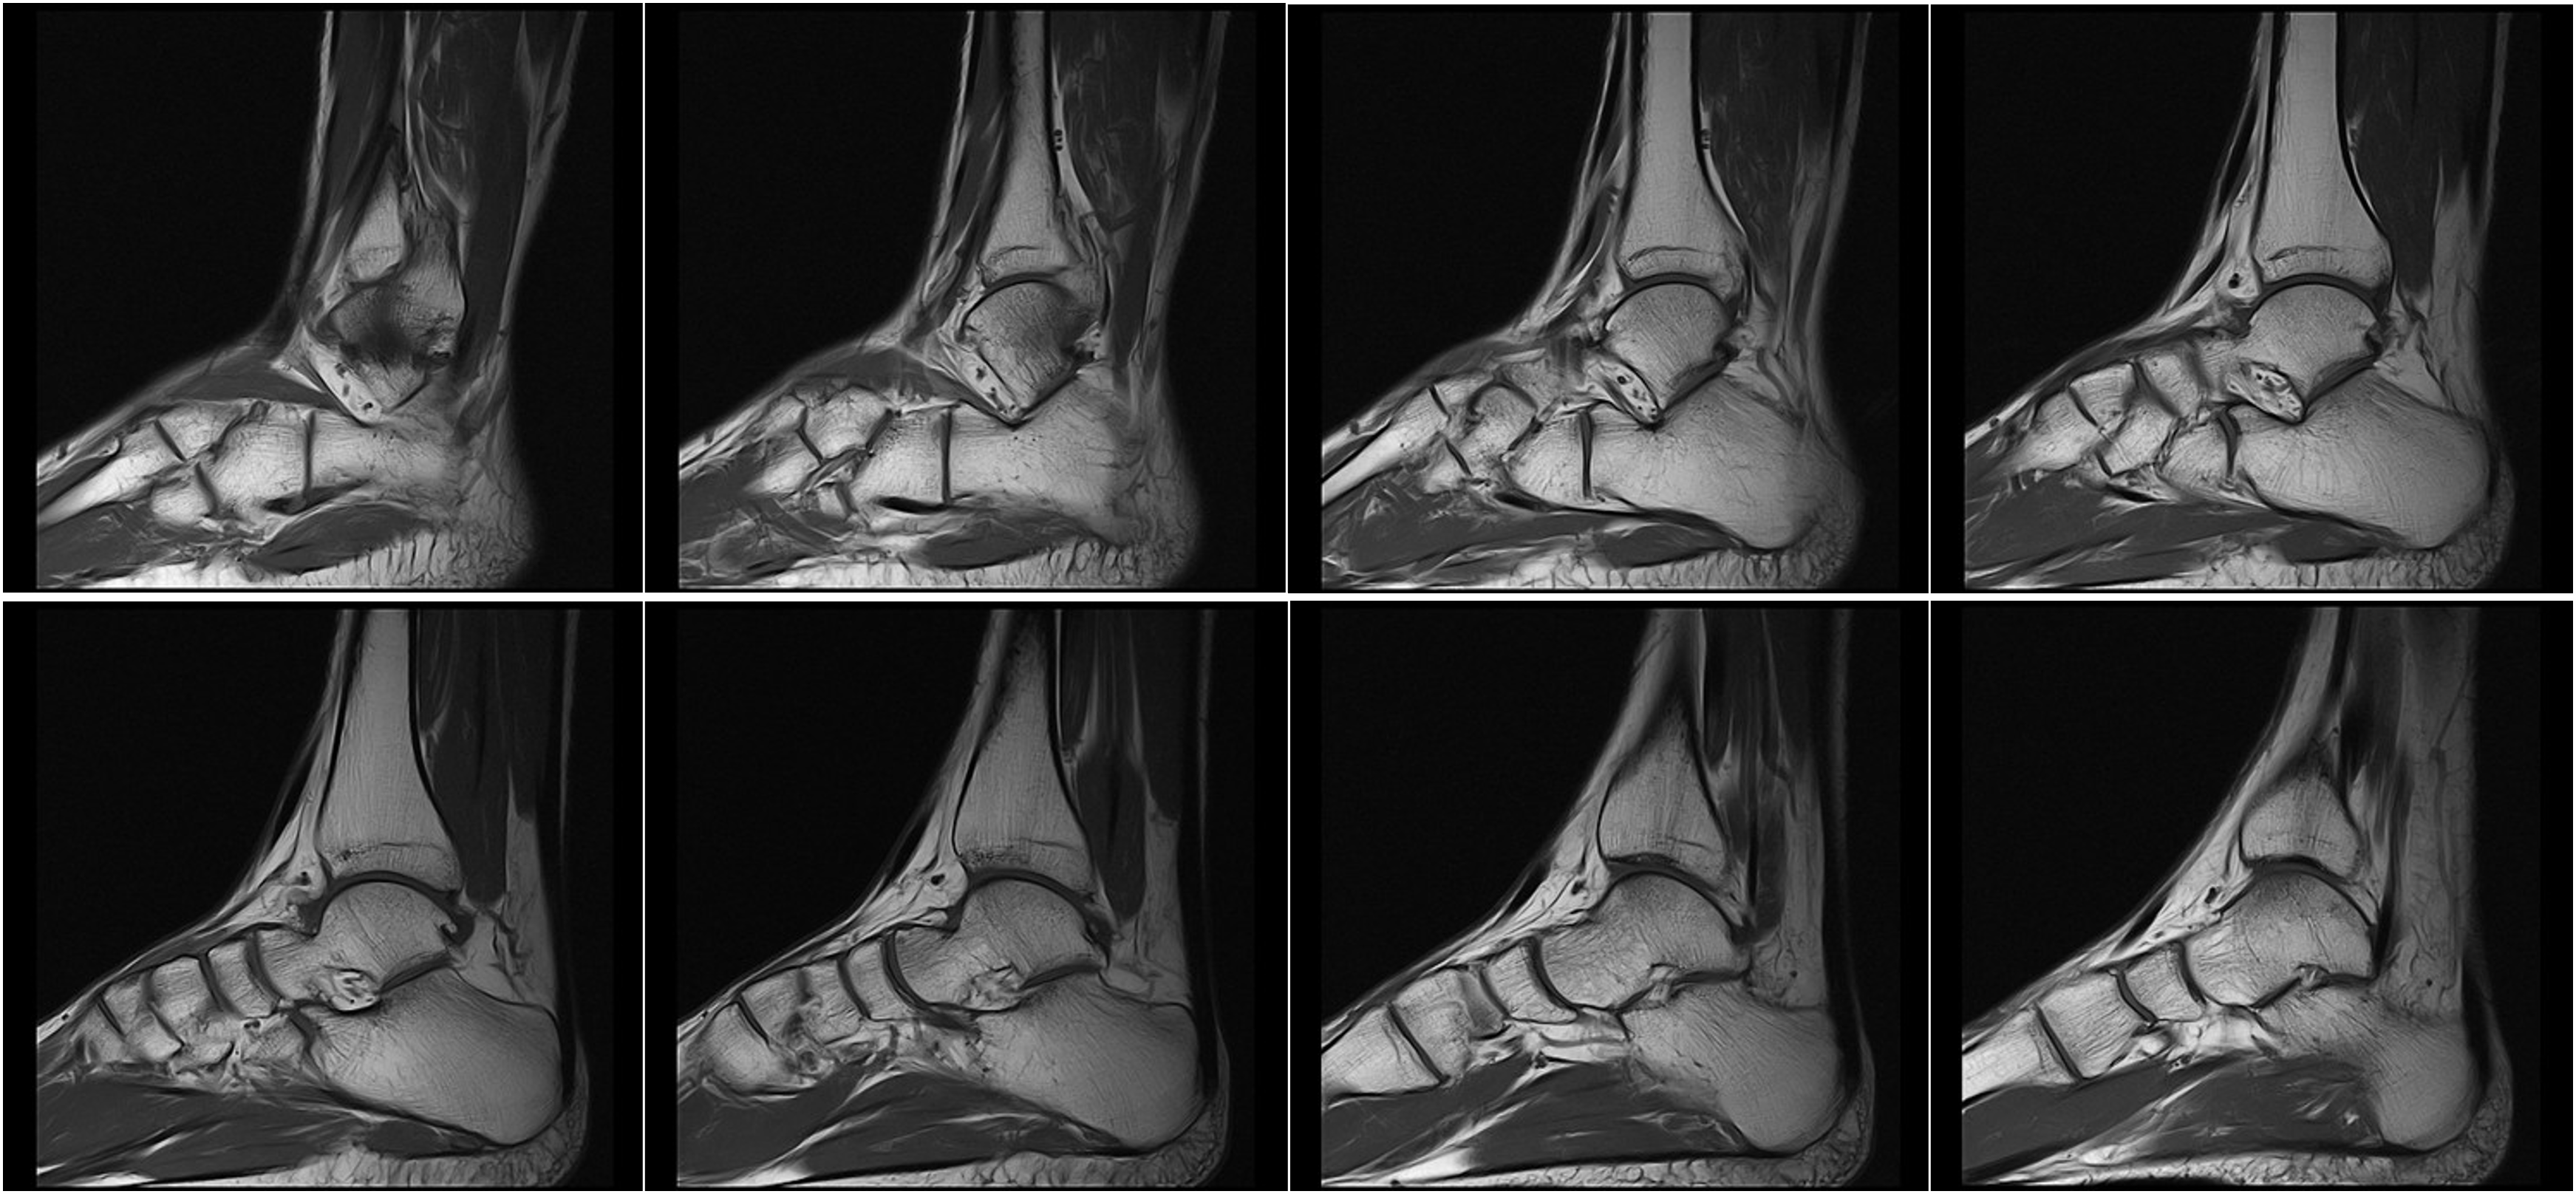

Hình ảnh lâm sàng